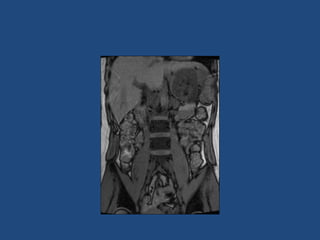

• CT better at eliminating malignancy

(dedicated CT looking at Hounsfield units (HU)

and washout characteristics)

– <10HU = benign (sens 71%, spec 100%)

• MRI may characterise phaeos better

• FDG-PET good for phaeos and cancer

• FNA – consider if cancer history and >10HU on CT

after exclusion of phaeo

Imaging

•

>6cm high suspicion of malignancy

3-6cm repeat imaging in 3-6M

Delayed washout on contrast is suggestive

most are often inhomogeneous, irregular

margins

• Look for invasion of IVC

• Always do CAP and consider bone scan and

pet if in doubt

• Don’t ever biopsy (tumour spill)